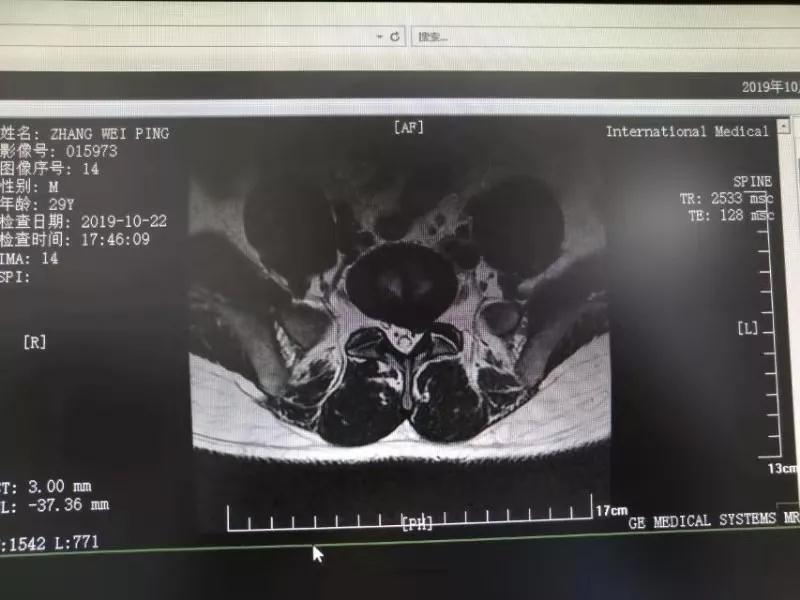

10月25日,29歲的患者小張了解到西安國際醫(yī)學(xué)中心骨科醫(yī)院專家云集,一大早便在家人的陪同下,來到西安國際醫(yī)學(xué)中心骨科醫(yī)院就診?!拔已闯掷m(xù)2年多,最近感冒后腰痛癥狀明顯加重了?!毙埫媛犊喑?yàn)殚L期腰痛、左下肢放射性疼痛,她晚上睡覺不能平躺,經(jīng)常疼得睡不著,需要口服止痛藥物才能有所緩解。走路走不了多遠(yuǎn)就開始腿抽的疼,嚴(yán)重影響到工作和生活。

結(jié)合患者的檢查以及年齡情況,王自立副院長推薦讓專門研究椎間孔鏡技術(shù)王雄勛主任給小張做微創(chuàng)的椎間孔鏡手術(shù)。該手術(shù)創(chuàng)傷很小,不影響脊柱的穩(wěn)定性,尤其適合于椎間盤突出的年輕患者,懷著對骨科醫(yī)院專家的信任,小張與家人商議后,接受手術(shù)治療。